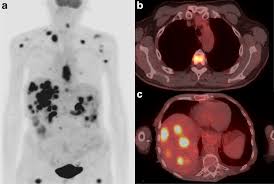

최첨단 현대의학으로 가장 적절한 방법이 양전자단층촬영술(Positron Emission Tomography, PET)이라고 나는 생각한다. PET는 체내 대사 변화를 촬영하는 기기로 CT나 MRI 다음에 개발된 영상장비이라고 한다.

요즘은 여기에 CT를 붙여서 PET 영상과 CT 영상을 융합해 서로 약점을 보완해 검사의 질을 더욱 높이고 있다고 한다.

여기에 방사성 핵종 F-18를 붙여(F-18 FDG라고 함) 혈관 주사하면 빨리 자리는 암세포는 포도당이 더 필요해 정상 세포보다 10∼100배 더 많이 모여들고 이를 방사능으로 촬영해 찾아낸다. 암이 1㎝만 돼도 10조개의 암세포가 있어 CT, MRI 소견이 애매한 경우 유용하게 쓰인다.

근래 들어 각 병원에서 될 수 있으면 높지 않은 가격에 PET 검진을 하기 위해 방사성 핵종의 주사량을 반으로 줄이고, 영상에는 차이가 없는 특별 프로토콜로 PET촬영을 하니 일석이조의 효과이라고 한다. 이 조치로 FDG 값도 절약하지만 방사선 조사량도 줄이게 됐다.

또 부수적으로 뇌 부분의 PET 영상으로 분석해 뇌졸중, 알츠하이머 치매도 조기 진단할 수 있다고 한다. 검사도 간단해서 정맥 주사를 맞고 1시간대기 후에 20분 정도 누운 상태로 촬영한다.